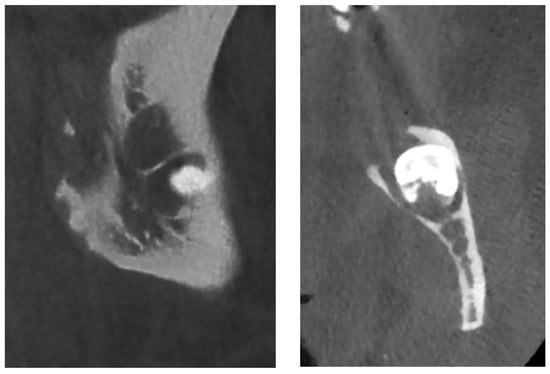

On CBCT X-ray, the distal root of the impacted tooth #38 was in contact with the upper wall of the left IAC, generating a discreet deformation of the canal (Figure 11). The cyst showing a multilocular aspect was located adjacent to the crown of tooth #38 and seemed to be attached to the tooth neck. The lesion extending slightly to the ascending branch of the mandible measured 17 mm in height, 21 mm in length and 10 mm in width. In its caudal part, the lesion was in contact with the upper wall of the IAC over about 13 mm. The wall was thinned but with little impact on its internal diameter. The vestibular and lingual cortex were also strongly thinned focally. There was no periosteal reaction or fracture at the mandibular angle. On the bases of these radiological findings, the differential diagnosis included DC, ameloblastoma, and odontogenic keratocyst.

Figure 11.

The lesion was enucleated in toto, and the teeth extracted (Figure 12) under general anesthesia, during which the ENT and maxillofacial surgeons proceeded with the placement of a mandibular osteosynthesis plate, followed by non-interruptive mandibulectomy, and finally, pelvi-glossectomy with tracheostomy and reconstruction with an anterolateral thigh flap and neck dissection. Histopathological examination of the cystic lesion allowed to diagnose a DC. The patient was followed regularly for two years, and no recurrence was observed.

Healing was uneventful and the patient had no complaints. Radiologically, at the 6- and 12-month follow-up (Figure 13), there was no reossification at the cystectomy and tooth 38 sites, which could be explained by a side effect of postoperative radiotherapy and chemotherapy. However, there were no signs of enlargement of the residual bone cavity, suggesting a recurrence of DC.